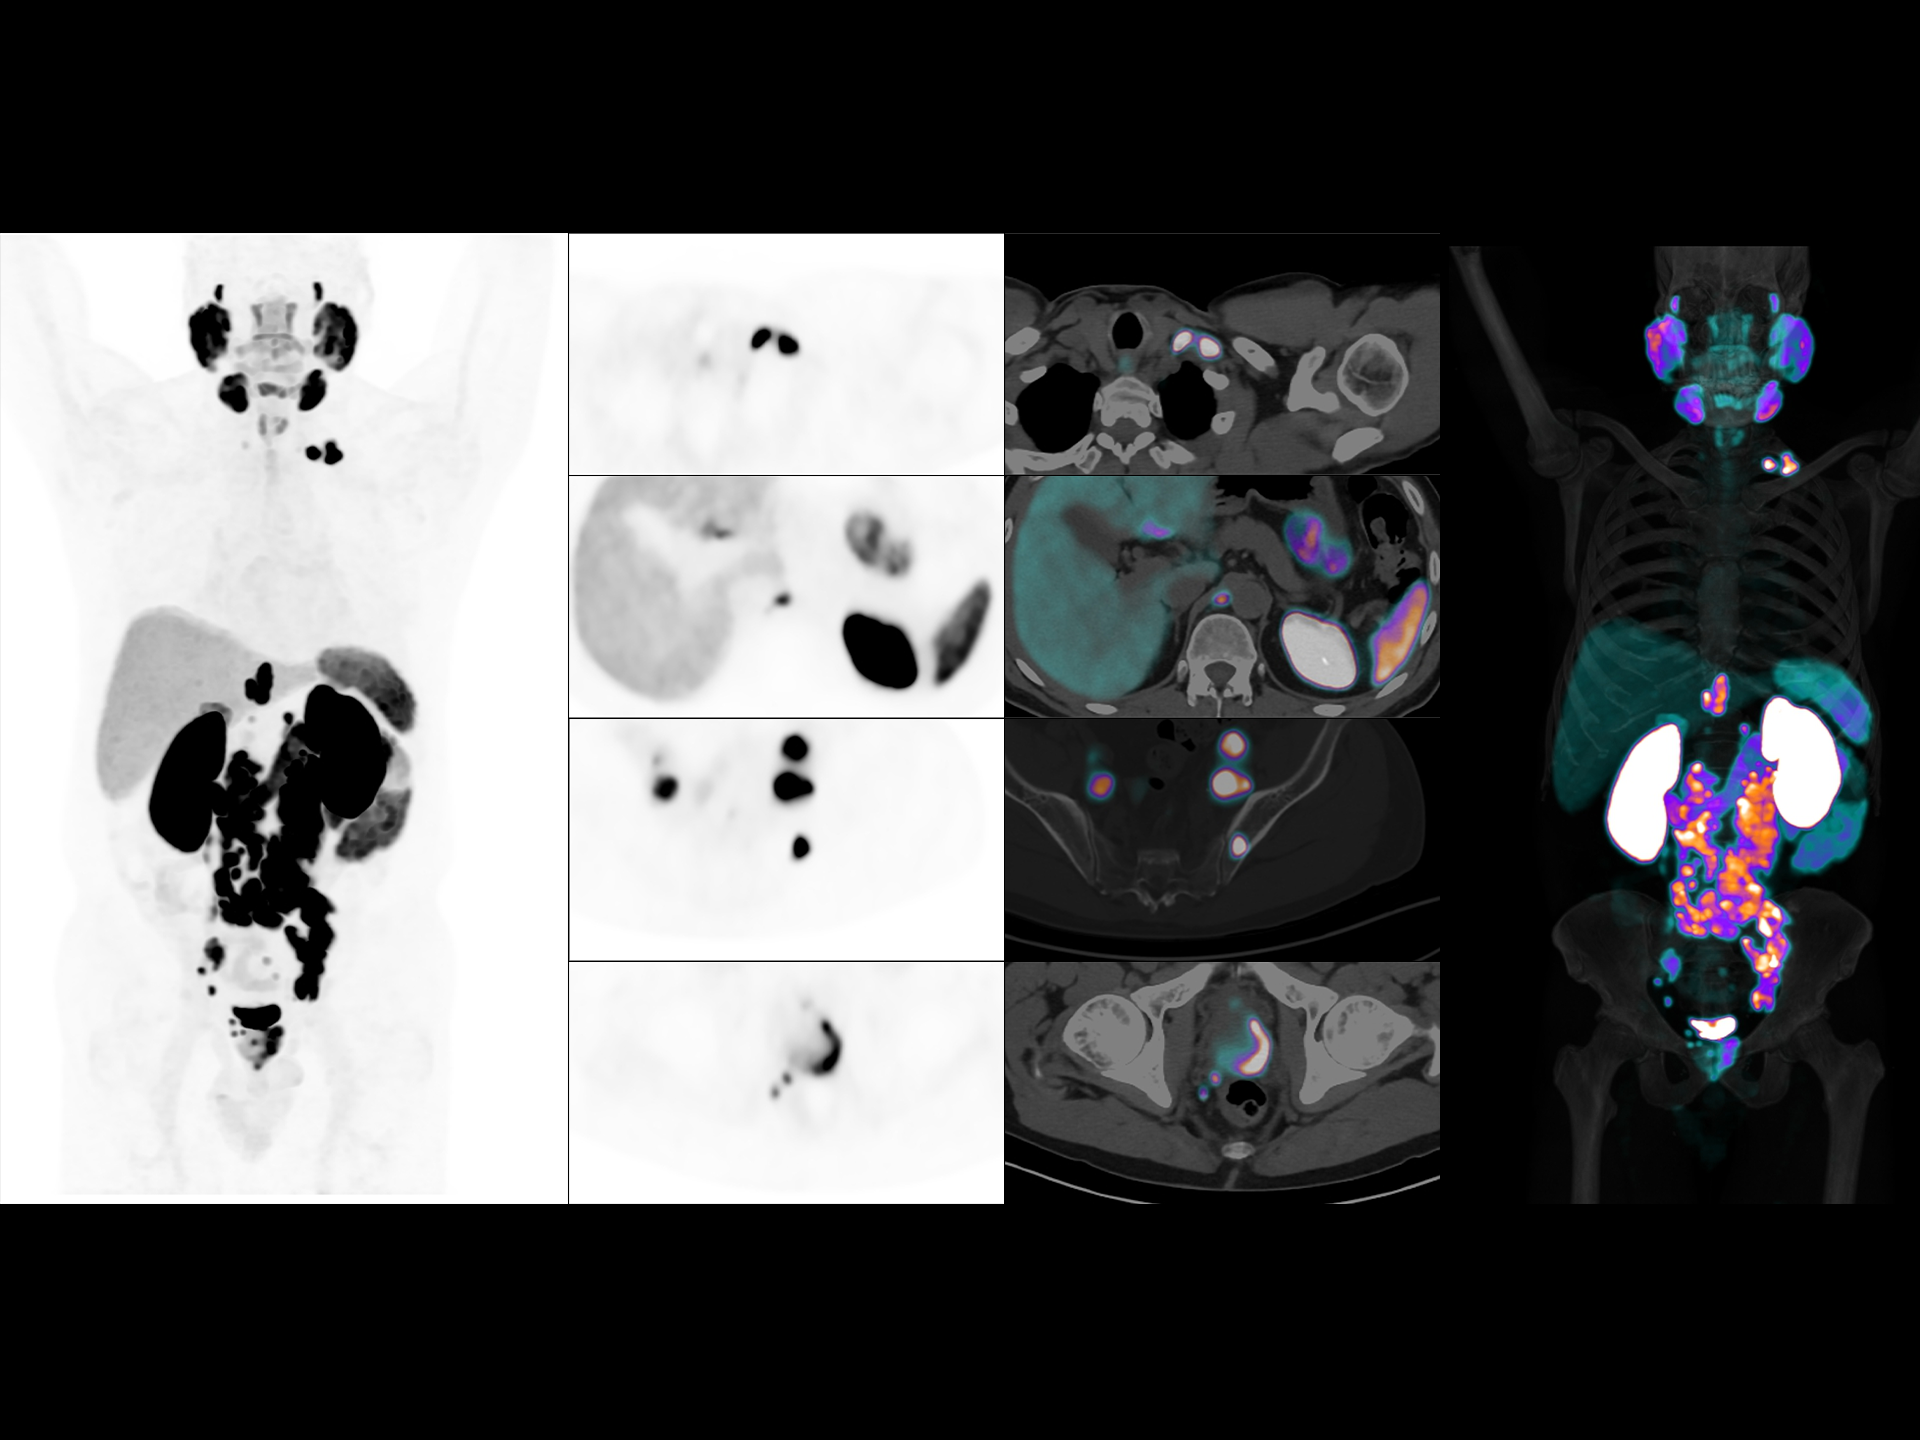

Leading TOF resolution that boosts small lesion detectability and clarity.

181 cps/kBq and more¹

High effective sensitivity that benefits from TOF gain leverages better diagnostic accuracy under low dose usage and fast scan time.